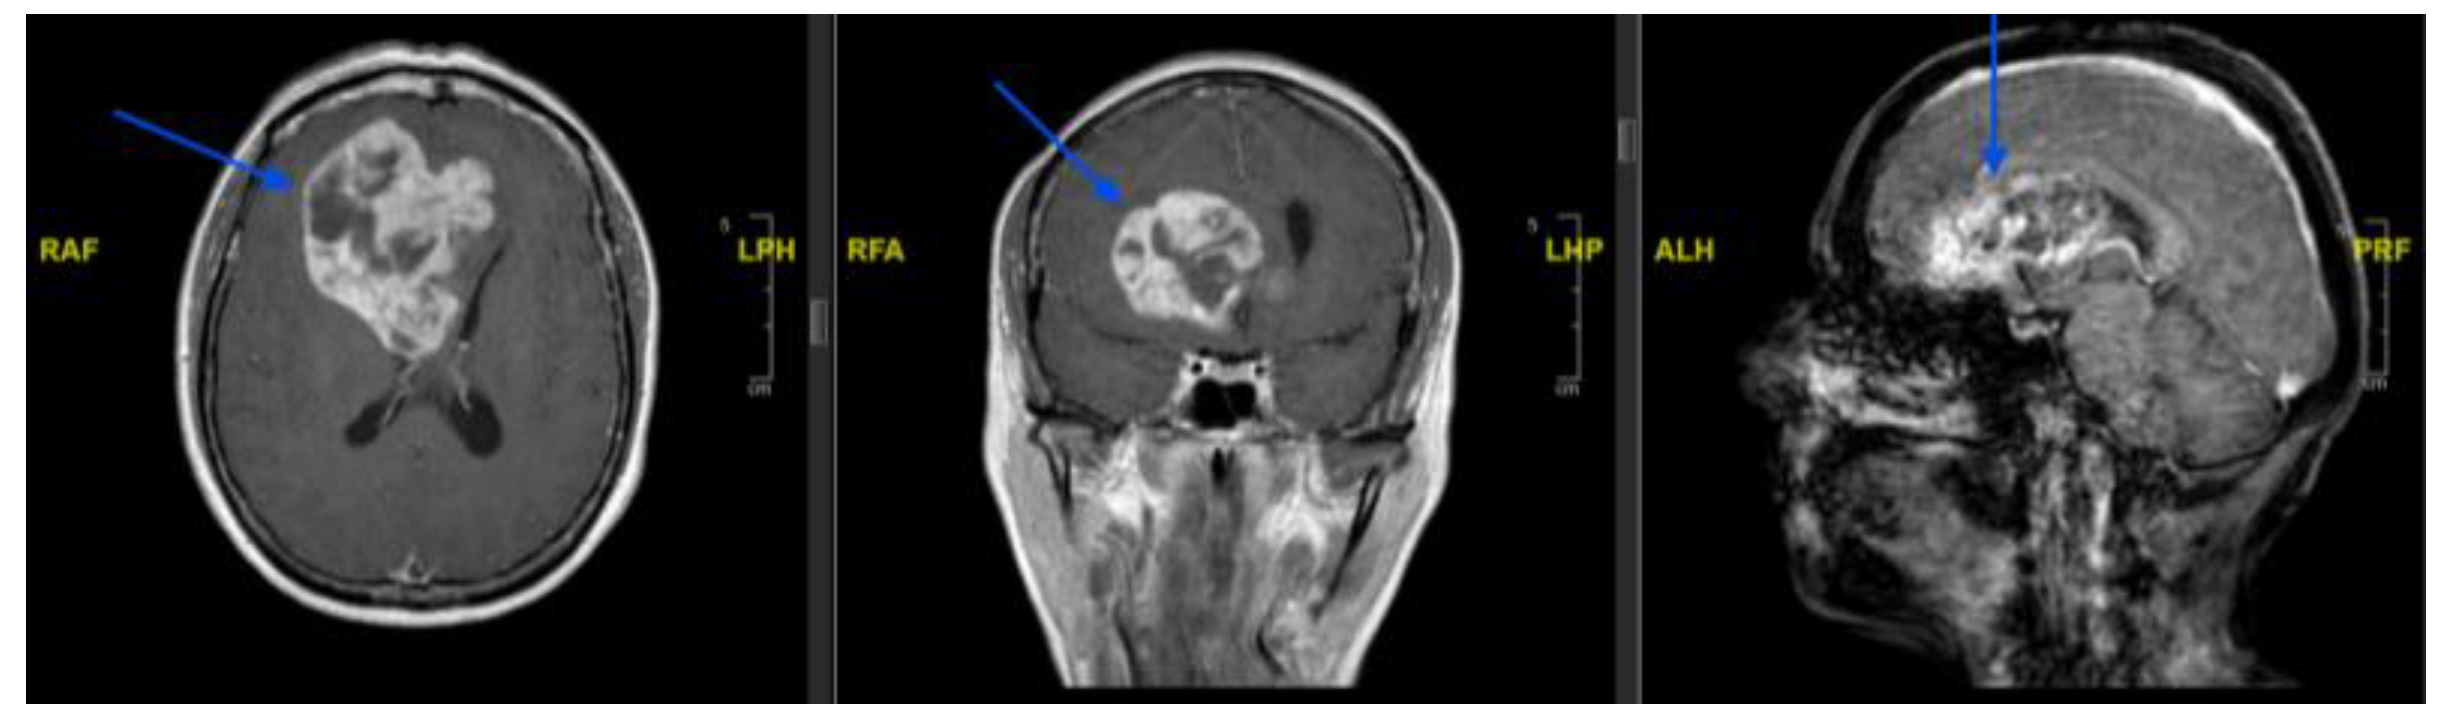

Background and Clinical Significance: Glioblastoma is the most common and aggressive primary malignant brain tumour in adults. Maximal safe surgical resection remains the cornerstone of treatment; however, tumour vascularisation may increase the risk of in-traoperative bleeding and complicate surgical management. Preoperative endovascular embolisation is commonly used for highly vascular intracranial tumours such as men-ingiomas, whereas its role in glioblastoma remains poorly defined. A focused literature review using the search string (((preoperative) AND (endovascular)) AND (embolization)) AND (glioblastoma) identified only two relevant publications, highlighting the scarcity of available evidence. In this context, we report a case series of three patients with intra-cranial lesions suspected to be high-grade gliomas who underwent preoperative angi-ographic evaluation and, when feasible, endovascular embolisation prior to surgical resection. Case Presentation: Three patients presenting with large intracranial lesions suggestive of high-grade glioma underwent preoperative digital subtraction angi-ography to assess tumour vascular supply (histological analysis confirmed the diagnosis of glioblastoma). In a 61-years-old woman with a right frontal tumour, selective catheteri-sation of a frontal branch of the right anterior cerebral artery enabled embolisation with coils, achieving partial tumour devascularisation before surgery. A second patient, a 53-year-old man with a large left temporo-fronto-insular mass extending to the corpus callosum, underwent embolisation of tumour feeders arising from the anterior choroidal artery using N-butyl cyanoacrylate and Lipiodol prior to resection. In a third case, a 77-year-old man with a left temporo-parietal lesion underwent preoperative angiography that demonstrated tumour capillary blush but no catheterisable feeding arteries, and embolisation was therefore not feasible. All patients subsequently underwent surgical resection without perioperative complications or new neurological deficits. Conclusions: Preoperative angiographic evaluation may help characterise tumour vascular supply in selected glioblastoma cases. When identifiable arterial feeders are present, endovascular embolisation may represent a feasible adjunct to facilitate surgical management. Further studies are required to better define the indications, safety profile, and potential benefits of this approach.